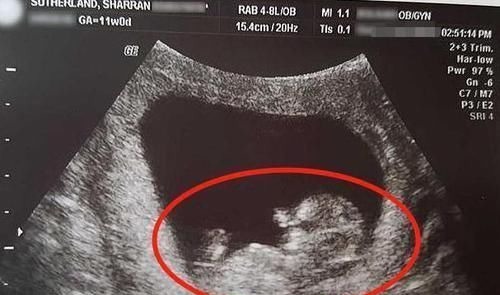

后遗症|女子怀孕14周流产,“胎儿”照片曝光!指甲盖都能看得清清楚楚

前段时间网络上有一组照片就火了起来,一位妈妈在非常不幸的状态下导致肚子里的宝宝流产。这位女子仅仅怀孕了14周就流产了,而且照片里的宝宝也被曝光了出来。因为这个妈妈非常在意这个宝宝,于是在流产了之后,母子之间有了一次亲密的接触。

在照片中我们可以清楚地看到,宝贝已经渐渐的成型了,虽然说宝宝的全身只有10厘米的长度,但是宝宝的小脚丫清晰的可见。宝宝的手也就更加清晰了,不仅能看到手指头的个数,而且手指甲盖都能看得清清楚楚。只是比较可惜的是,这么一个完美的生命,却因为一些种种原因,导致没有来到这个世界上。换做是哪一个父母都没有办法接受眼前的事实,更何况是孩子的妈妈呢?